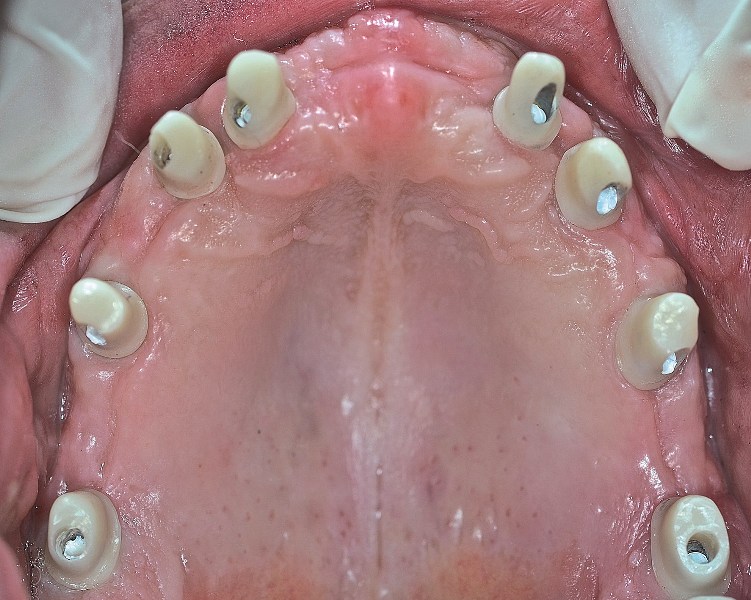

W mojej opinii, w naprawdę wyjątkowych przypadkach można umocować 12 zębów na stałe na 4 implantach. Warunki muszą być jednak bardzo sprzyjające. Aby wszczepić wystarczająco długie i szerokie implanty do utrzymania 12 zębów, kość musi być obfita. Bardziej realistyczną liczbą jest 5 do 8 implantów. Wówczas nie są one przeciążone, a siły zgryzu rozkładają się prawidłowo. Ostateczna ilość implantów przy pełnej rekonstrukcji to decyzja bardzo indywidualna i złożona. Składają się na nią  takie czynniki, jak jakość i ilość kości, tonacja mięśni twarzy, rozmiar szczęki i żuchwy pacjenta.

Pełna rekonstrukcja uzębienia jest jedną z najtrudniejszych procedur w stomatologii. Jeżeli odbudowa protetyczna uzębienia obejmuje także własne zęby pacjenta, to możemy wykorzystać korony, mosty i implanty występujące pojedynczo lub połączone w mosty. Pełną rekonstrukcję zaczynamy od wstępnej analizy jamy ustnej, modeli pacjenta stworzonych na podstawie wycisku, zdjęć rtg oraz tomografii. Na podstawie tych informacji wykonujemy projekt przyszłego uzębienia. Dalszy przebieg leczenia jest uzależniony od tego, jakie procedury należy wykonać, zanim możliwa będzie implantacja. Po wszczepieniu implantów następuje etap uzupełnień tymczasowych/próbnych, na podstawie których pacjent może ocenić estetykę i wygodę przyszłych uzupełnień stałych. Pacjent ma szansę zgłosić swoje uwagi do zaproponowanych uzupełnień stałych i uzyskać efekt końcowy, który go całkowicie ustatysfakcjonuje